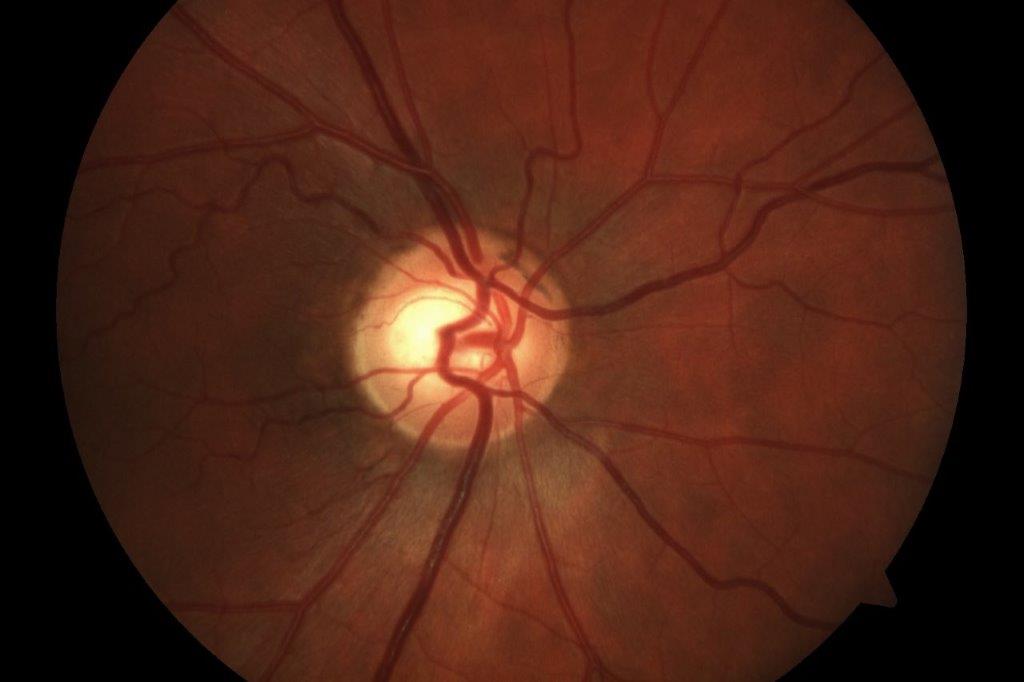

Examination revealed visual acuity of 6/9 in the affected eye, with OCT confirming persistent subretinal fluid. Autofluorescence imaging showed only minimal scarring from previous laser treatment with no evidence of RPE atrophy at the fovea. OCT-angiography ruled out secondary choroidal neovascularisation.

The results were notable from an anatomical standpoint. At two-month follow-up, OCT demonstrated complete resolution of subretinal fluid, while autofluorescence imaging confirmed preservation of RPE integrity at the fovea with no treatment-related damage.

However, functional outcomes were more complex. Despite excellent anatomical resolution, the patient reported minimal subjective visual improvement, with visual acuity remaining stable at 6/9. This likely reflects chronic photoreceptor changes from prolonged fluid accumulation, highlighting the importance of early intervention in CSCR.

Interestingly, the patient expressed significant satisfaction with the anatomical resolution. Since one of his main concerns had been progressive photoreceptor atrophy from persistent subretinal fluid, achieving complete fluid resolution provided considerable psychological benefit. He was discharged to a local ophthalmologist and at his most recent follow-up (over six months post-treatment), there has been no recurrence.